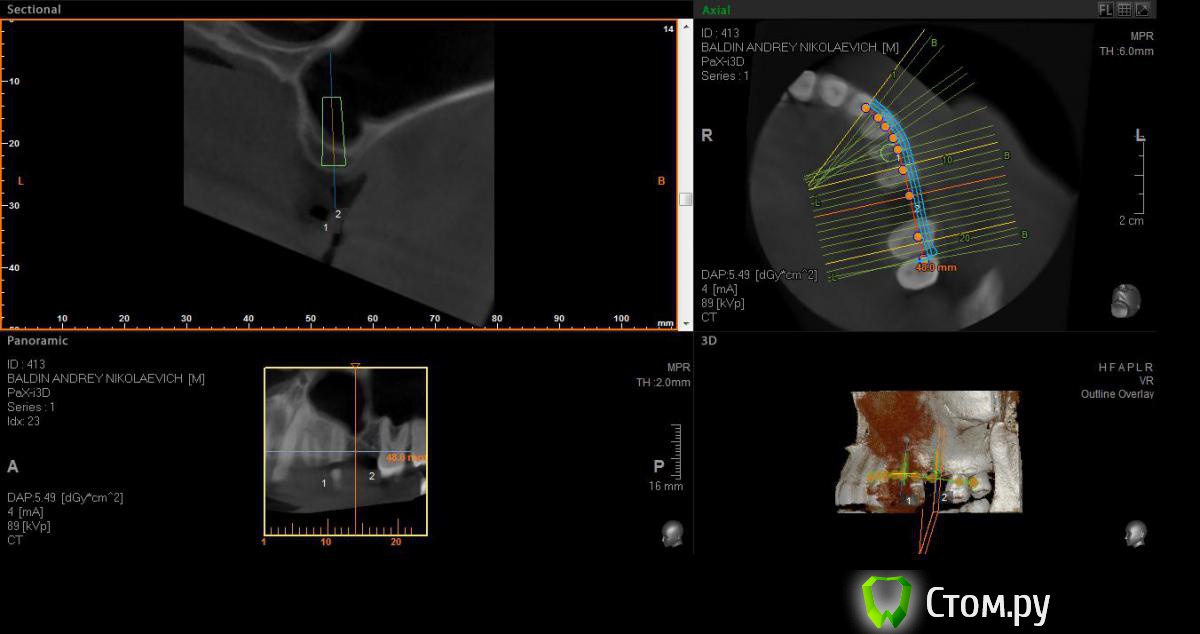

faity Опубликовано 25 апреля, 2014 Поделиться Опубликовано 25 апреля, 2014 доброго времени суток.планирую имплантацию в области 2.4 одномоментно, 2.6 с синусомAnkylos 4,5/9,5 в оба места.вопрос: какова вероятность обойтись закрытым синусом при толщине кости чуть более 4 мм в области 2.6, планирую BioOss с PRP, не получу ли я этот винт в пазухе носа через 3-4 месяца? Ссылка на комментарий

red_butler Опубликовано 25 апреля, 2014 Поделиться Опубликовано 25 апреля, 2014 срезы выставлены не правильно. Но похоже все показания к открытому синуслифту с имплантацией Ссылка на комментарий

kriokov Опубликовано 26 апреля, 2014 Поделиться Опубликовано 26 апреля, 2014 срезы выставлены не правильно. Но похоже все показания к открытому синуслифту с имплантацией+100, про срезы. Надо панорамную кривую полноценно выставлять, и тогда прога автоматически кроссы нарежет перпендикулярно к панорамной кривой. Ссылка на комментарий

faity Опубликовано 27 апреля, 2014 Автор Поделиться Опубликовано 27 апреля, 2014 исправил срезы, перепланировал ход.оба импланта по 11 мм, открытый синус, если открою перегородку септы- расширюсь дистальнее и откушу её, если нет, то в её пределах графт(примерно 1,5гр)+стружка(примерно 2-3 гр)+prp(флакон), ФДМ.критика приветствуется Ссылка на комментарий